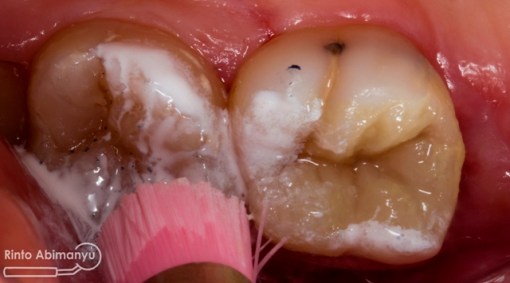

Seluruh jaringan karies dibuang menggunakan bur tungsten carbide low speed, dilanjutkan pembuatan artificial wall menggunakan komposit dengan bantuan matriks greatercurve.